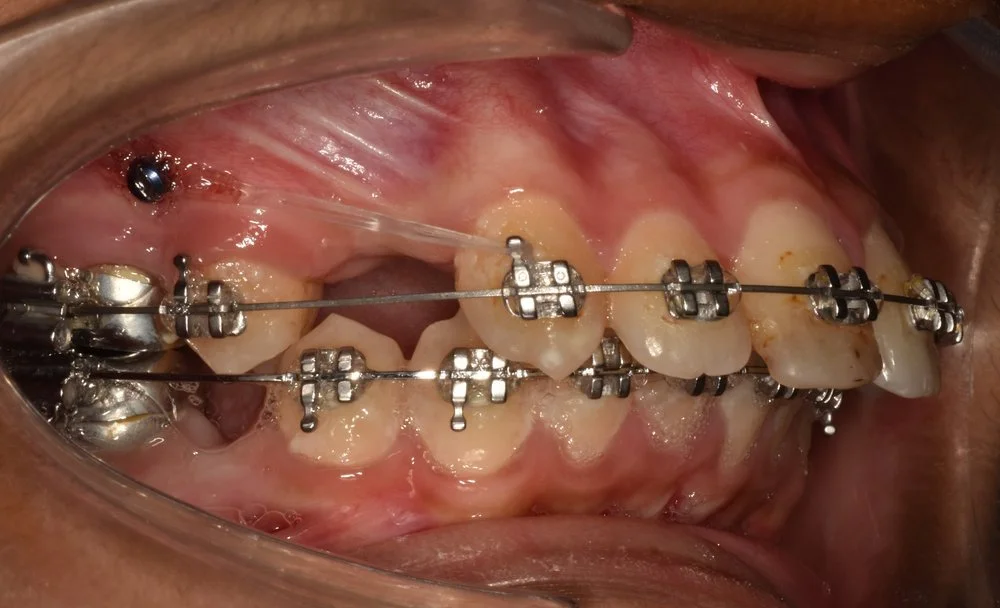

Extra-radicular implants